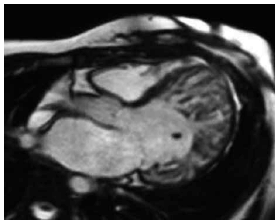

Mulher, 50 anos, apresenta quadro clínico de insuficiência cardíaca. Realiza ecocardiograma que mostra fração de ejeção do ventrículo esquerdo de 35%. Opta-se por realizar ressonância magnética cardíaca para pesquisa etiológica, demonstrada na imagem a seguir.

Enunciado 4231923-1

(BRAUNWALD, E. et al. (Ed.) Tratado de Doenças Cardiovasculares. 11 Ed. Rio de Janeiro: Editora Elsevier, 2022. 2 vol)

Com base nas informações apresentadas, considera-se como etiologia: